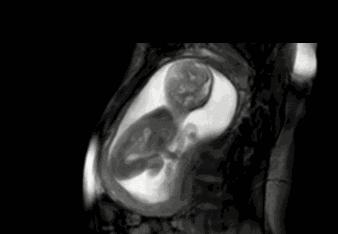

如果之前胎动不是很频繁,突然频繁就需要引起注意了,这可能是胎儿缺氧或者其他不好的情况。

胎儿发生缺氧时,原本安静的宝宝会突然变得很胎动频繁,当缺氧持续加重时,胎动又逐渐减少,甚至危及他的生命。

感觉胎动没有规律、胎儿没有力气,异常活跃之后变得特别安静,这种情况都要留意。

所以胎动如果是生理性的话是正常的,宝妈们不用太着急,如果是病理性的需要及时到医院治疗,寻求医生帮助。